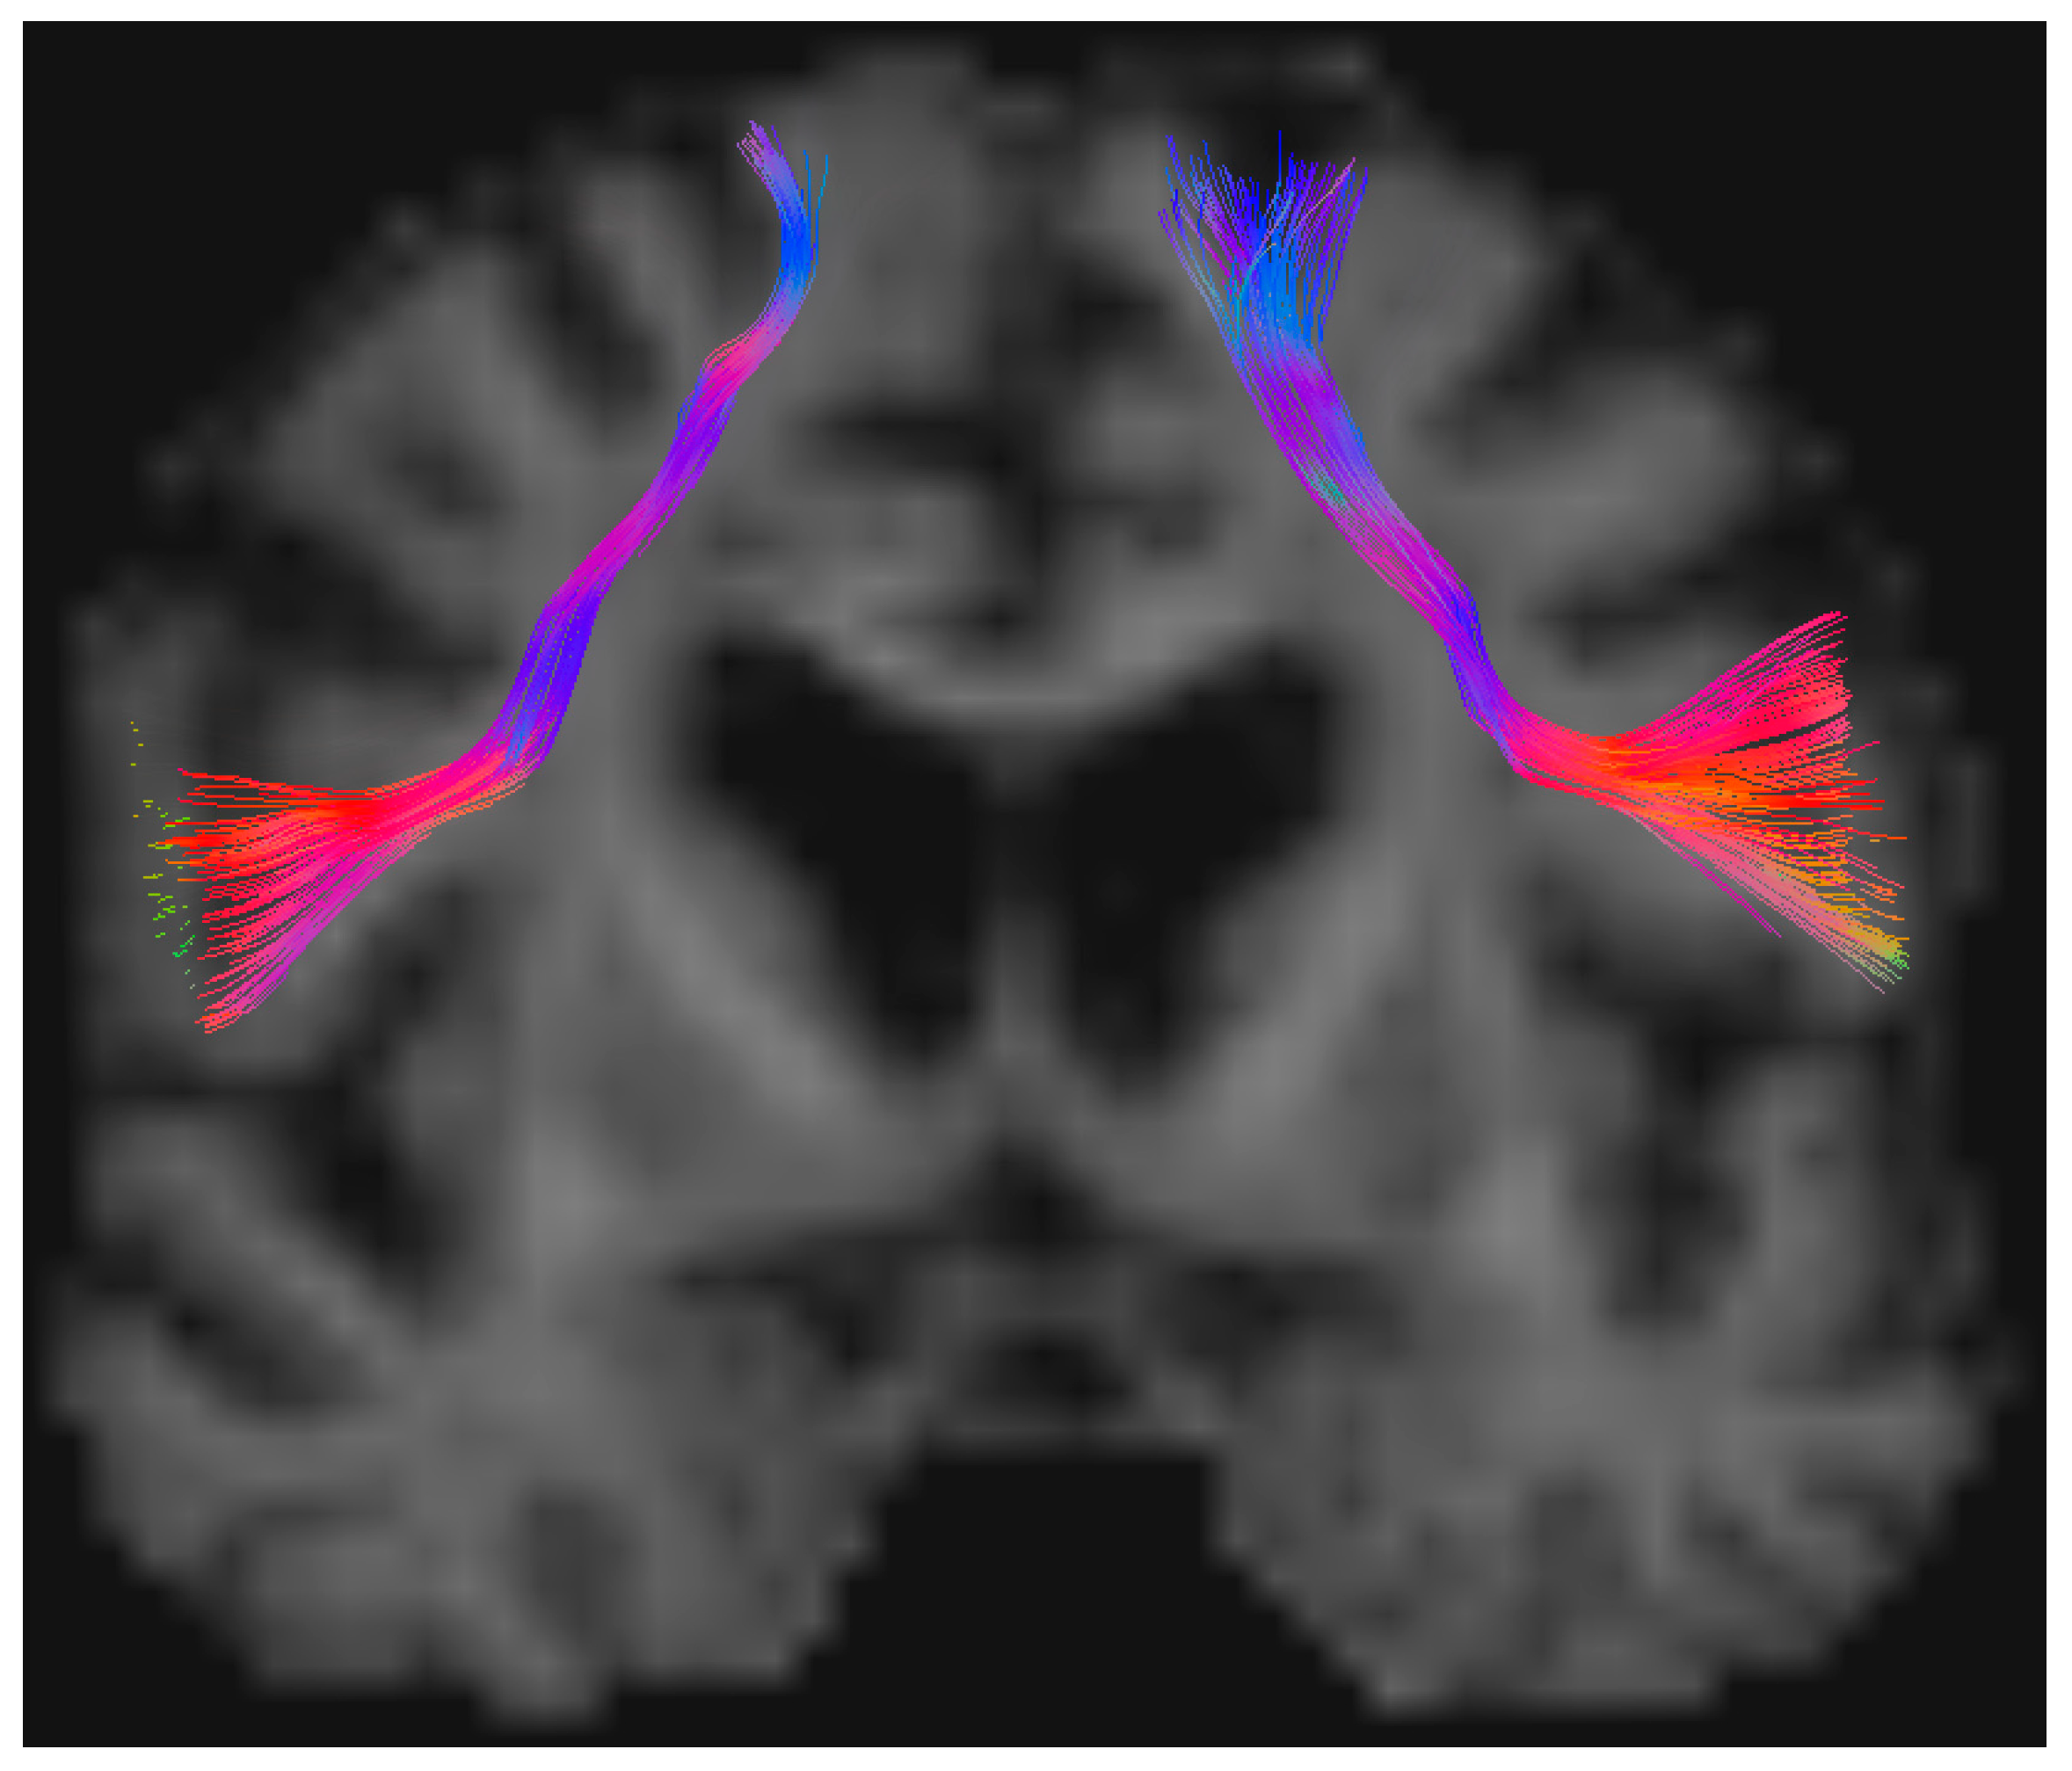

2.3. Imaging and Tractography Data

3.8. Illustrative Case